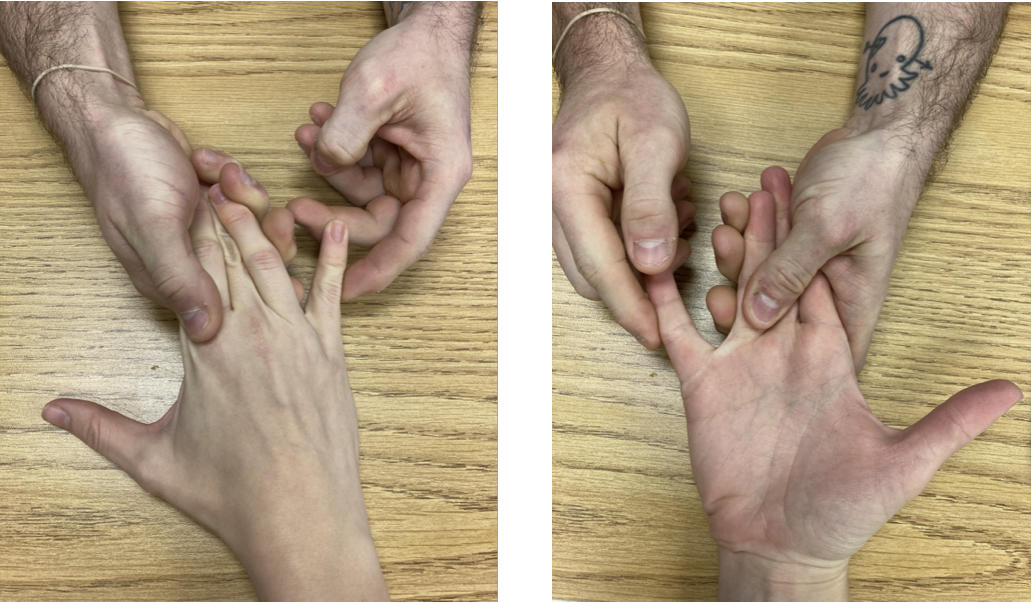

发现扳机指和掌腱膜掌腱膜之间的联系

发现扳机指和掌腱膜挛缩症之间的联系作者:Tayer Roost 参考文献:Yang, Gehring, M.、Bou Zein Eddine, S. 和 Hettinger, P. (2019)。狭窄之间的关联...